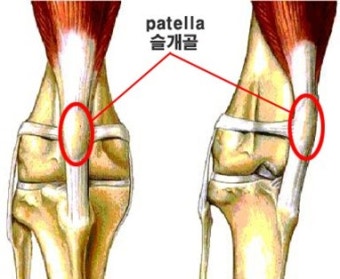

1. 슬개골 탈구란?

슬개골 탈구는 쉽게 말해 무릎뼈가 제자리를 벗어나는 증상입니다. 사람으로 치면 무릎이 '툭' 하고 빠지는 느낌인데, 강아지에게는 이게 지속적으로 반복될 수 있는 문제죠.